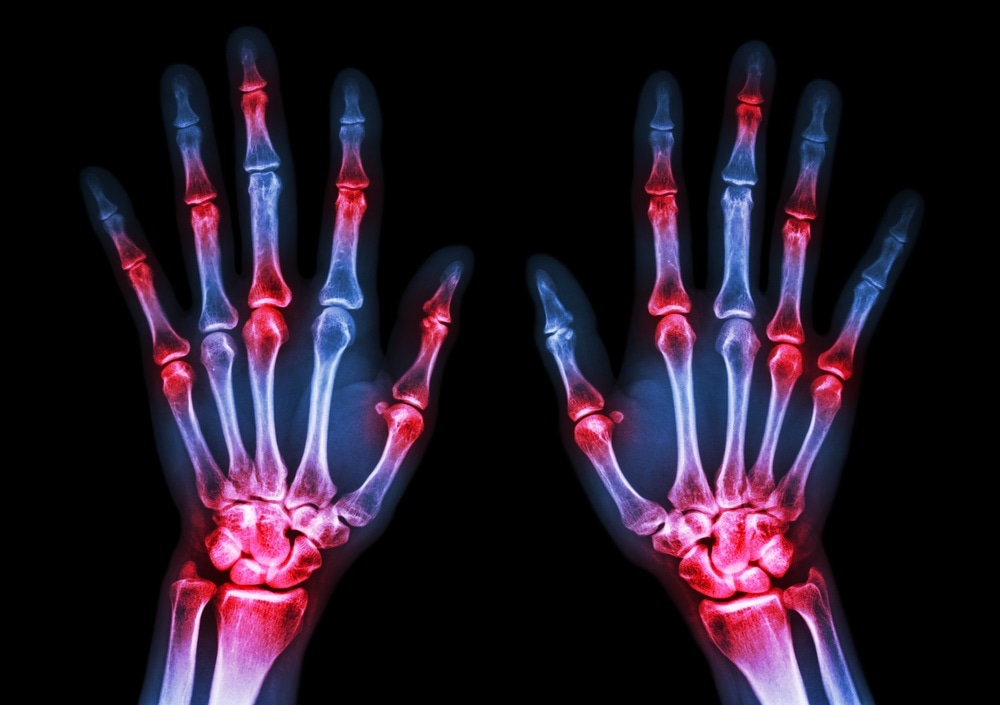

rheumatoid arthritisImage Credit: Puwadol Jaturawutthichai / Shutterstock.com